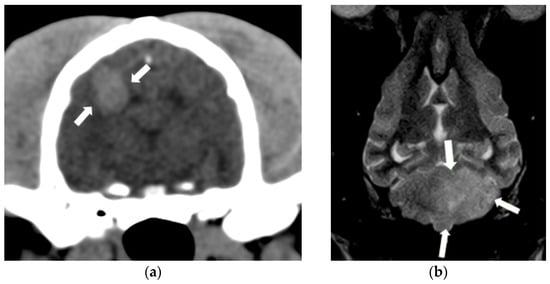

2.2. Cerebrovascular Disease

2.3. Idiopathic Vestibular Syndrome